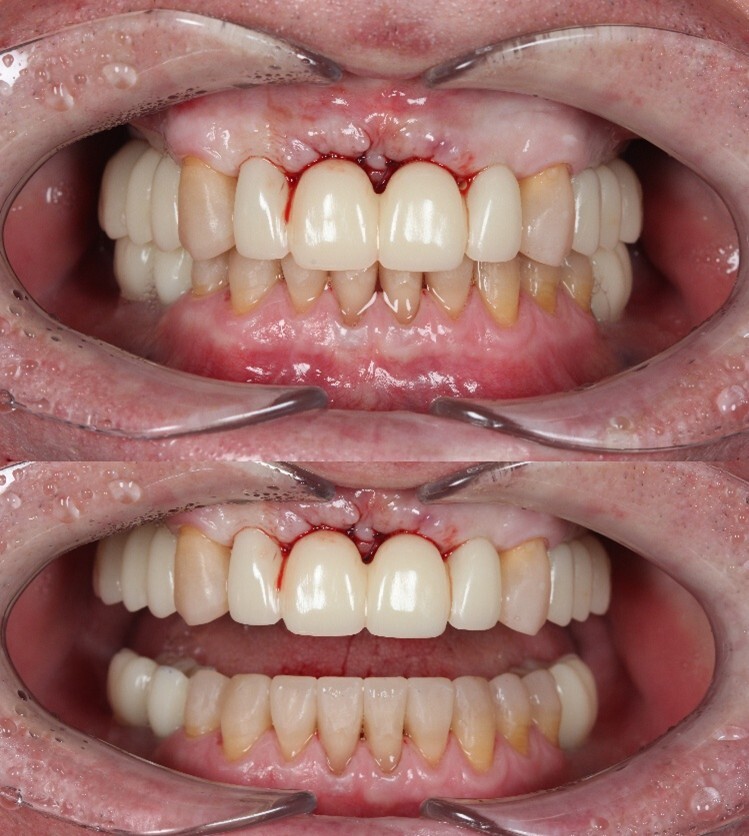

Спустя две недели произведена фиксация временных коронок.

Параллельно я удалил два центральных верхних резца, после чего были зафиксированы все остальные временные коронки.

Подчеркну - коронки временные (!), все они будут заменены на постоянные.

А как стало на промежуточном этапе:

Согласитесь, выглядит очень даже неплохо, если опустить цвет.